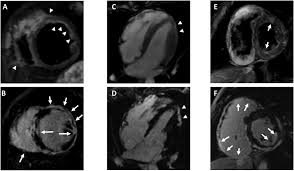

Combined Electrocardiography Coronary Angiography And Magnetic Resonance Imaging For The Diagnosis Of Viral Myocarditis A Case Report

Combined Electrocardiography Coronary Angiography And Magnetic Resonance Imaging For The Diagnosis Of Viral Myocarditis A Case Report from www.spandidos-publications.com

Journal of the american college of cardiology vol. More specifically, it is described as. Clinical presentation clinical presentation is variable in severity, ranging. Myocarditis cardiosclerosis is a pathology in which parts of the myocardium involved in inflammation die and are replaced by connective tissue. Mrt in der diagnose und monitoring neurodegenerativer erkrankungen. Khk, ischämietest bei bekannter khk). It is considered the most. Sie kann akut oder chronisch verlaufen.